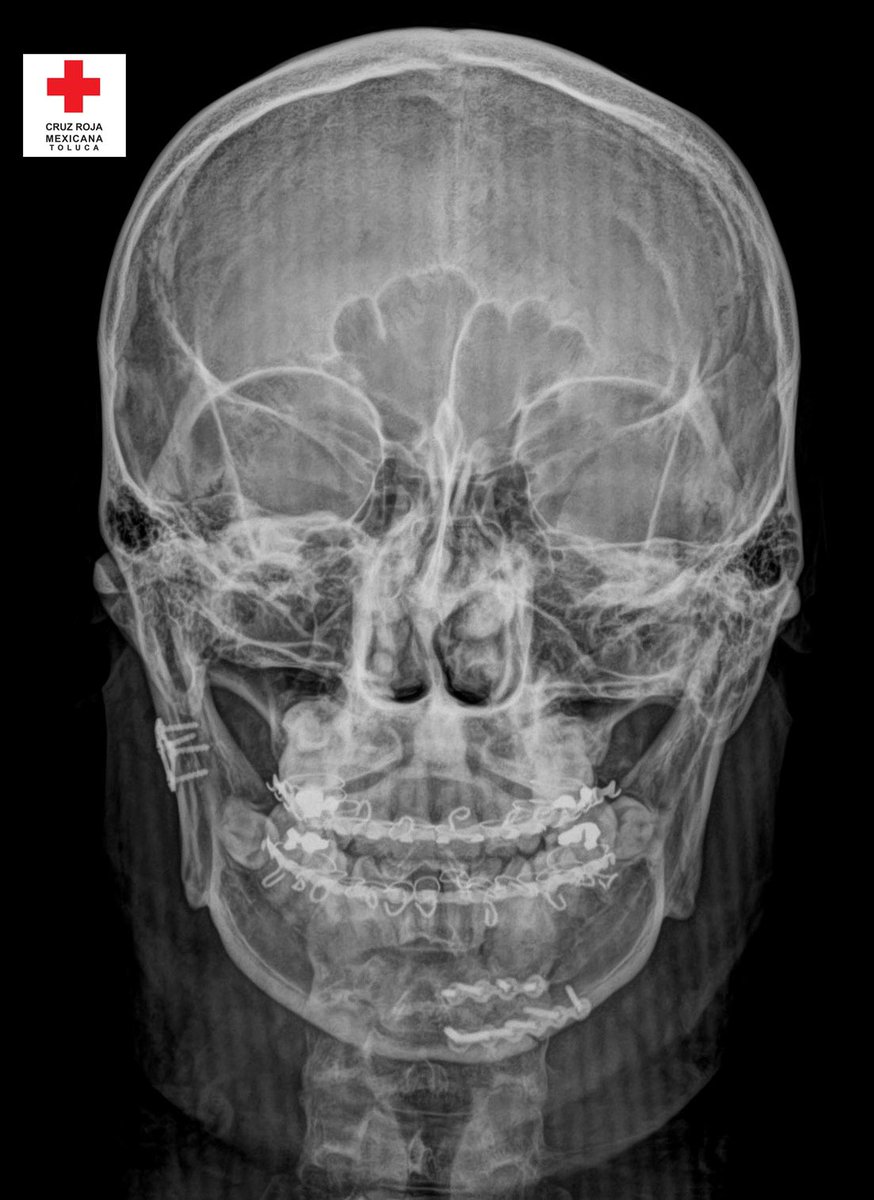

Nuestro equipo médico y dental realizó la primera cirugía Maxilo Facial, a bajo costo, en los quirófanos de Cruz Roja Toluca. La exitosa intervención quirúrgica fue una Reducción Abierta y Fijación Interna (RaFi) doble de mandíbula, mediante la colocación de dos placas metálicas y la

La exitosa intervención quirúrgica fue una Reducción Abierta y Fijación Interna (RaFi) doble de mandíbula, mediante la colocación de dos placas metálicas y la

fijación intermaxilar mediante un sistema Arco barra de Erich. El paciente, un joven de 26 años que sufrió un accidente vehicular, fue dado de alta esta tarde y convalece en su domicilio. Muchas felicidades al equipo médico que labora en nuestra institución #AyudarNosMueve